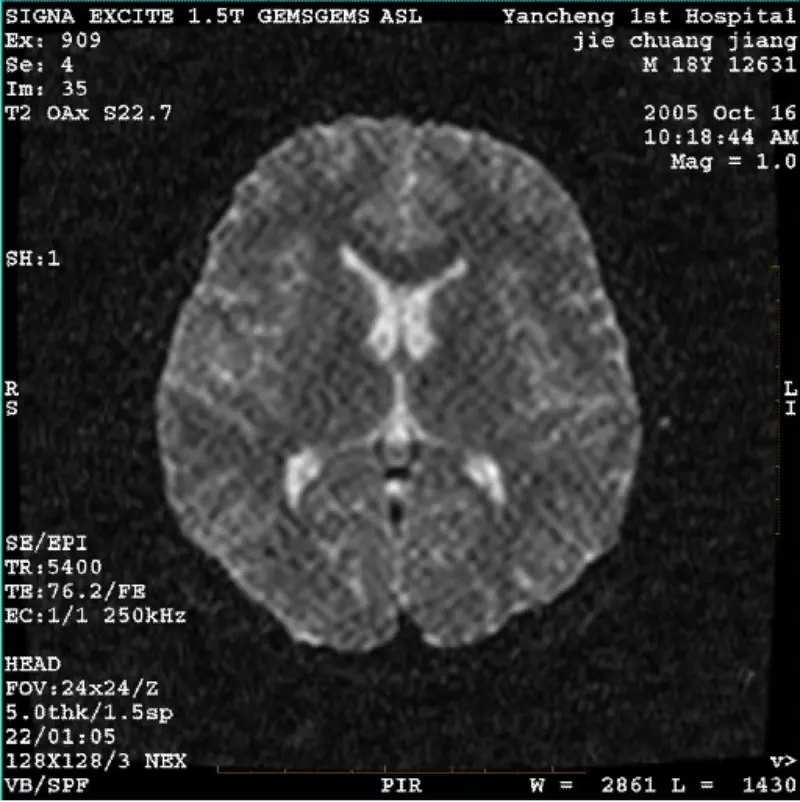

ອ່ານຕື່ມລະບົບ: 1.5T Signa Twin Excite II (ຊອບແວເວີຊັນ 11.0M4) ບັນຫາ/ອາການ DWI (ໂຫມດຊູມແລະໂຫມດທັງຫມົດ) ແລະ fiesta (ໂຫມດຊູມແລະໂຫມດທັງຫມົດ) ມີຮູບພາບ ເບິ່ງເຫັນ reticulate ຫຼື corduroy artifact ບໍ່ວ່າຈະໃນເວລາທີ່ການນໍາໃຊ້ coil ຮ່າງກາຍຫຼືຫົວ coil, ຮູບພາບປົກກະຕິອື່ນໆເບິ່ງຄືວ່າປົກກະຕິ